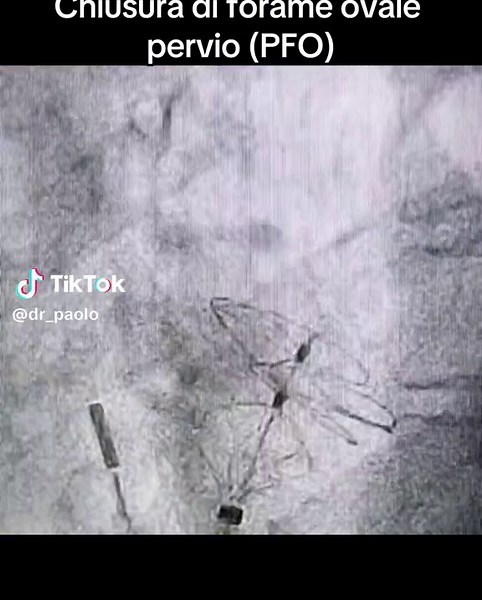

Chiusura di Forame Ovale Pervio: Guida Completa

TikTok

dr_paolo

296mii vizualizări

11 dec. 2023

0:46